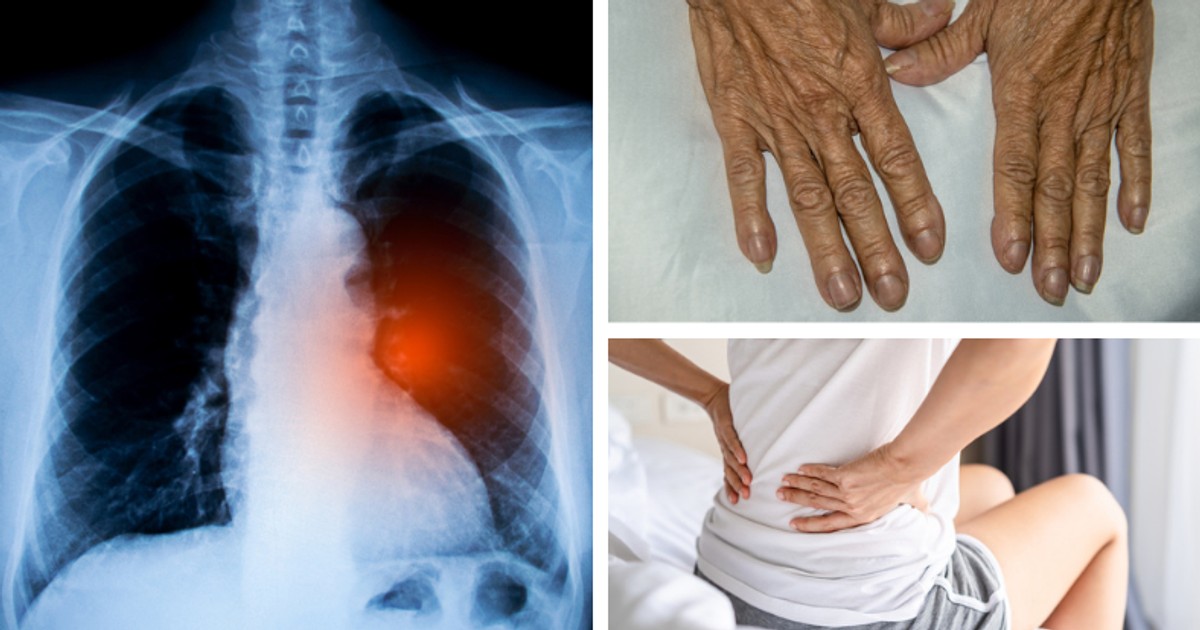

<ol><li>Wród niepokojcych objawów, na które warto zwróci uwag, naley wyróni krwioplucie, wiszczcy oddech oraz ból w klatce piersiowej</li><li>Objawy raka puc czsto pojawiaj si nawet sze miesicy przed… [+4993 chars]